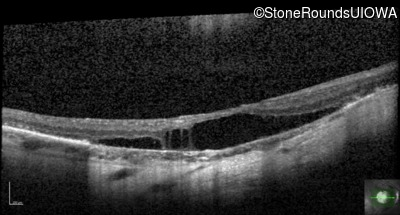

This 15 year old male had a macular abnormality noted two weeks ago when he was refracted for his first pair of glasses. Bone spicule-like pigmentation was first noticed a year later (age 16) during a routine follow-up eye exam.

Age at visit: 16 years

Age at visit: 18 years